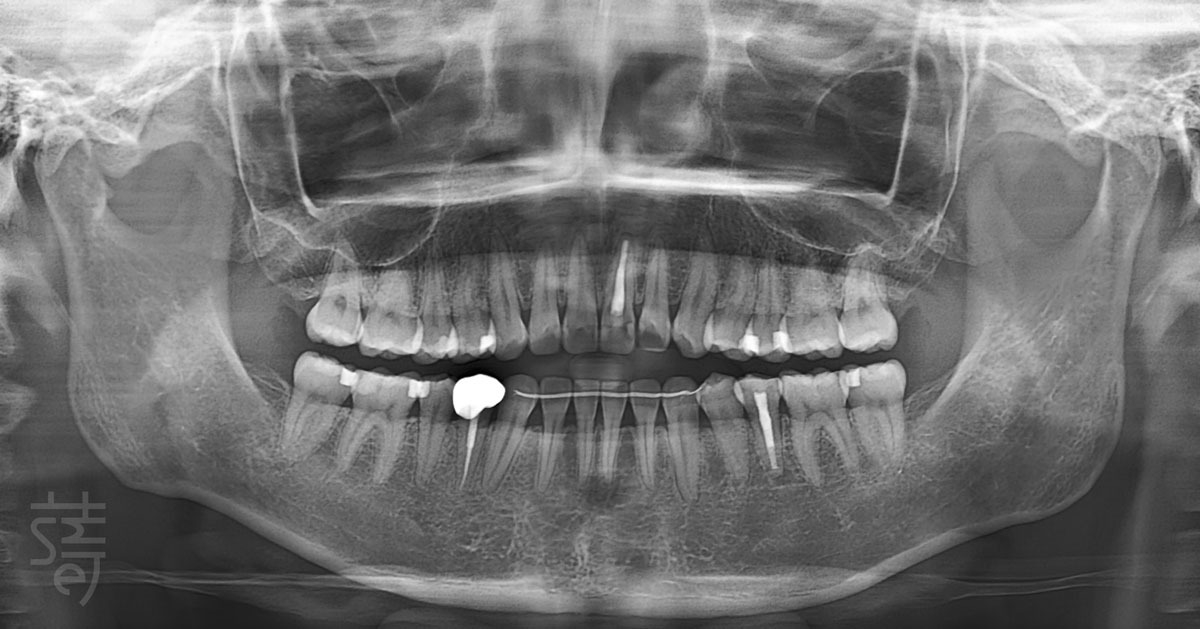

在進入貼片設計之前,林醫師先為張小姐進行一次完整而細緻的檢查。

林醫師評估的重點,至少包含以下六個關鍵維度:

① 牙齒牙齦的健康狀態

② 齒色的層次與透亮度

③ 牙齒牙齦型態及比例

④ 整體排列與微笑曲線

⑤ 動態笑容的肌肉運作

⑥ 最終形塑的風格感受

這些元素彼此牽動,缺一不可。

也因此,蒔美團隊透過一系列數位化檢測,從口內結構、臉部比例到肌肉運作層面,全面檢視張小姐的口內外條件。當所有基礎被妥善整理後,瓷牙貼片的設計與療程,才正式展開。

Before any veneer design began, the Smile Dental team conducted a thorough evaluation. A truly considered veneer plan looks beyond surface fixes—assessing dental and gum health, shade and translucency, proportions, smile line, muscle movement, and overall style.

Health always comes first. Only after confirming the mouth can support veneers long term did the Smile Dental team move forward, using digital tools to assess everything from oral structure to facial balance. With the foundation in place, the aesthetic work could begin.

過去左上門牙曾因童年蛀牙接受根管治療與假牙修復,加上長期飲用咖啡,原生牙齒隨著時間逐漸染色,使整體齒色偏暗,並與假牙之間拉開色差。在不同光線下,笑容呈現出不均勻的層次感,成了她心中始終放不下的小細節。

相較於齒色,牙齒比例帶來的影響往往較少被察覺,卻格外關鍵。張小姐的前牙比例偏小,使微笑時的線條略顯拘謹,視覺焦點不易聚攏,也少了她心中那份俐落而有精神的神采。

在瓷牙貼片設計中,牙齦比例往往是影響成敗的另一關鍵。為了讓整體效果更為自然,林醫師建議搭配牙齦微整形,重新調整牙齒與牙齦的視覺關係。

透過細緻的修整與貼片形態調整,原本略顯扁短的牙齒輪廓,得以重新取得視覺空間,讓長寬比例從接近一比一的方形,過渡至更接近五比四的和諧比例。